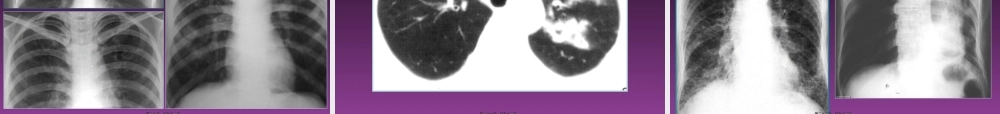

呼吸系统基本(jīběn)病变的X线表现X线征象(表现)--基本病变(bìngbiàn)--病变(bìngbiàn)性质--疾病诊断临床诊断:临床表现(病史、体检等)--一种、几种可能的诊断;影像资料等各种辅助检查--验证或否定(fǒudìng)、排除影像诊断:影像征象--病理基础--疾病可能;结合临床表现--最合理的解释第一页,共五十二页。第一页,共五十二页。(一)支气管改变病因,常规X线主要为肺的间接(jiànjiē)表现1.阻塞性肺气肿--活塞机制2.(1)局限性第二页,共五十二页。第二页,共五十二页。左侧(zuǒcè)一侧性阻塞性肺气肿左下肺局限性阻塞性肺气肿第三页,共五十二页。第三页,共五十二页。代偿(dàichán)ɡ性肺气肿第四页,共五十二页。第四页,共五十二页。(2)弥漫性第五页,共五十二页。第五页,共五十二页。第六页,共五十二页。第六页,共五十二页。肺气肿第七页,共五十二页。第七页,共五十二页。2.阻塞(zǔsè)性肺不张--完全阻塞(zǔsè),肺外压迫,肺内疤痕收缩;一侧性,肺叶,肺段,肺小叶;第八页,共五十二页。第八页,共五十二页。第九页,共五十二页。第九页,共五十二页。右上叶不张第十页,共五十二页。第十页,共五十二页。右下叶不张左下叶不张第十一页,共五十二页。第十一页,共五十二页。右中叶(zhōngyè)不张第十二页,共五十二页。第十二页,共五十二页。一侧性肺不张第十三页,共五十二页。第十三页,共五十二页。右上中央(zhōngyāng)型肺癌第十四页,共五十二页。第十四页,共五十二页。(二)肺部病变1.渗出与实变2.定义(dìngyì)、病理3.X线表现第十五页,共五十二页。第十五页,共五十二页。全肺叶(fèiyè)实变第十六页,共五十二页。第十六页,共五十二页。SARS肺水肿支气管气像(airbronchogram)第十七页,共五十二页。第十七页,共五十二页。支气管气像(airbronchogram)第十八页,共五十二页。第十八页,共五十二页。各种(ɡèzhǒnɡ)实变:云雾、云絮、斑片、大片、团片第十九页,共五十二页。第十九页,共五十二页。2.增殖与腺泡结节定义、病理(bìnglǐ)及X线表现第二十页,共五十二页。第二十页,共五十二页。浸润(jìnrùn)型肺结核中的渗出、增殖和干酪坏死病灶第二十一页,共五十二页。第二十一页,共五十二页。3.纤维化(实质、间质)定义(dìngyì)、病理及X线表现第二十二页,共五十二页。第二十二页,共五十二页。第二十三页,共五十二页。第二十三页,共五十二页。4...